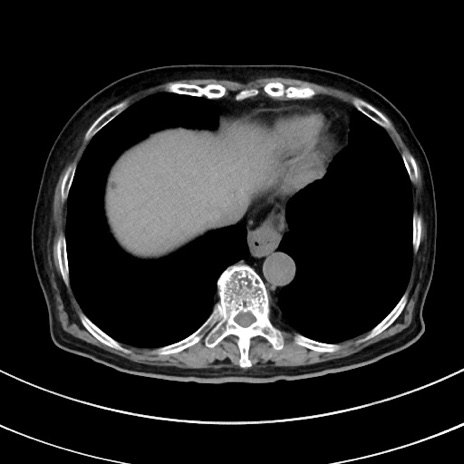

冠状断像

【症例】70歳代 女性

【主訴】心窩部痛

【現病歴】延髄病変の精査・加療にて神経内科入院中。本日より心窩部痛あり。

【身体所見】右下腹部を中心に圧痛と反跳痛あり。